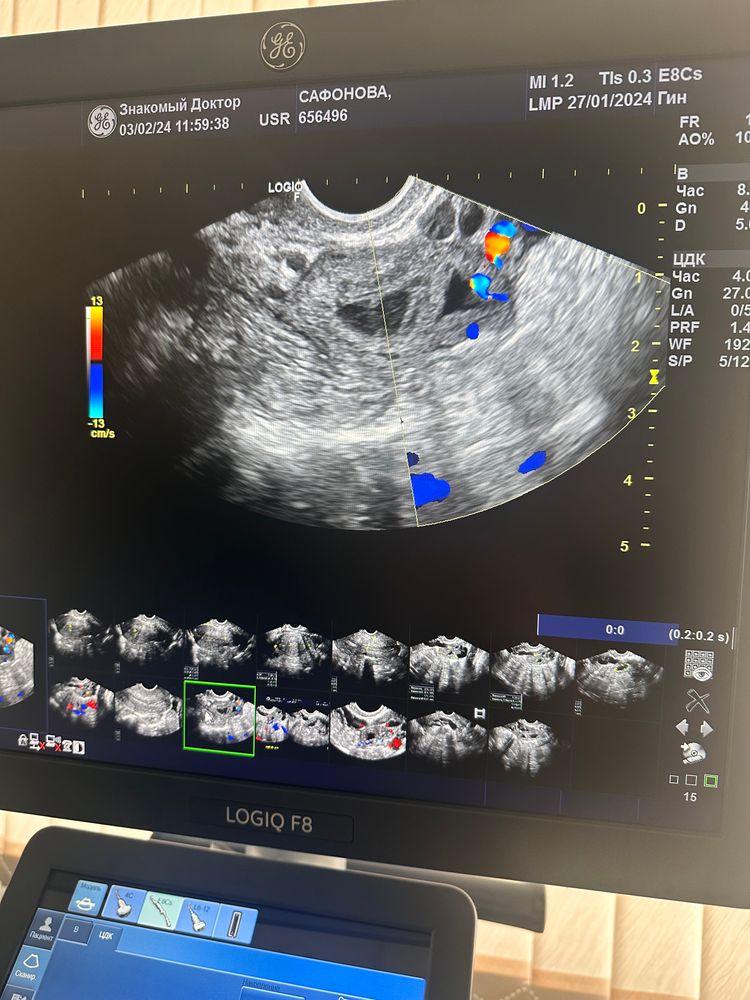

03.02 Вторая фалликулометрия (8 день цикла)

В левом уменьшенная киста ЖТ с прошлого цикла (17 мм) и вместо доминантного фолликула ЖТ размером 10 мм.

Отсюда вывод, Овуляция произошла скорее всего либо на 6 или 7 или утром на 8 день цикла.

В левом киста ЖТ с прошлого цикла уменьшается , размер 16 мм, ЖТ этого цикла выросло , размер тоже 16 мм., кровоток хороший.